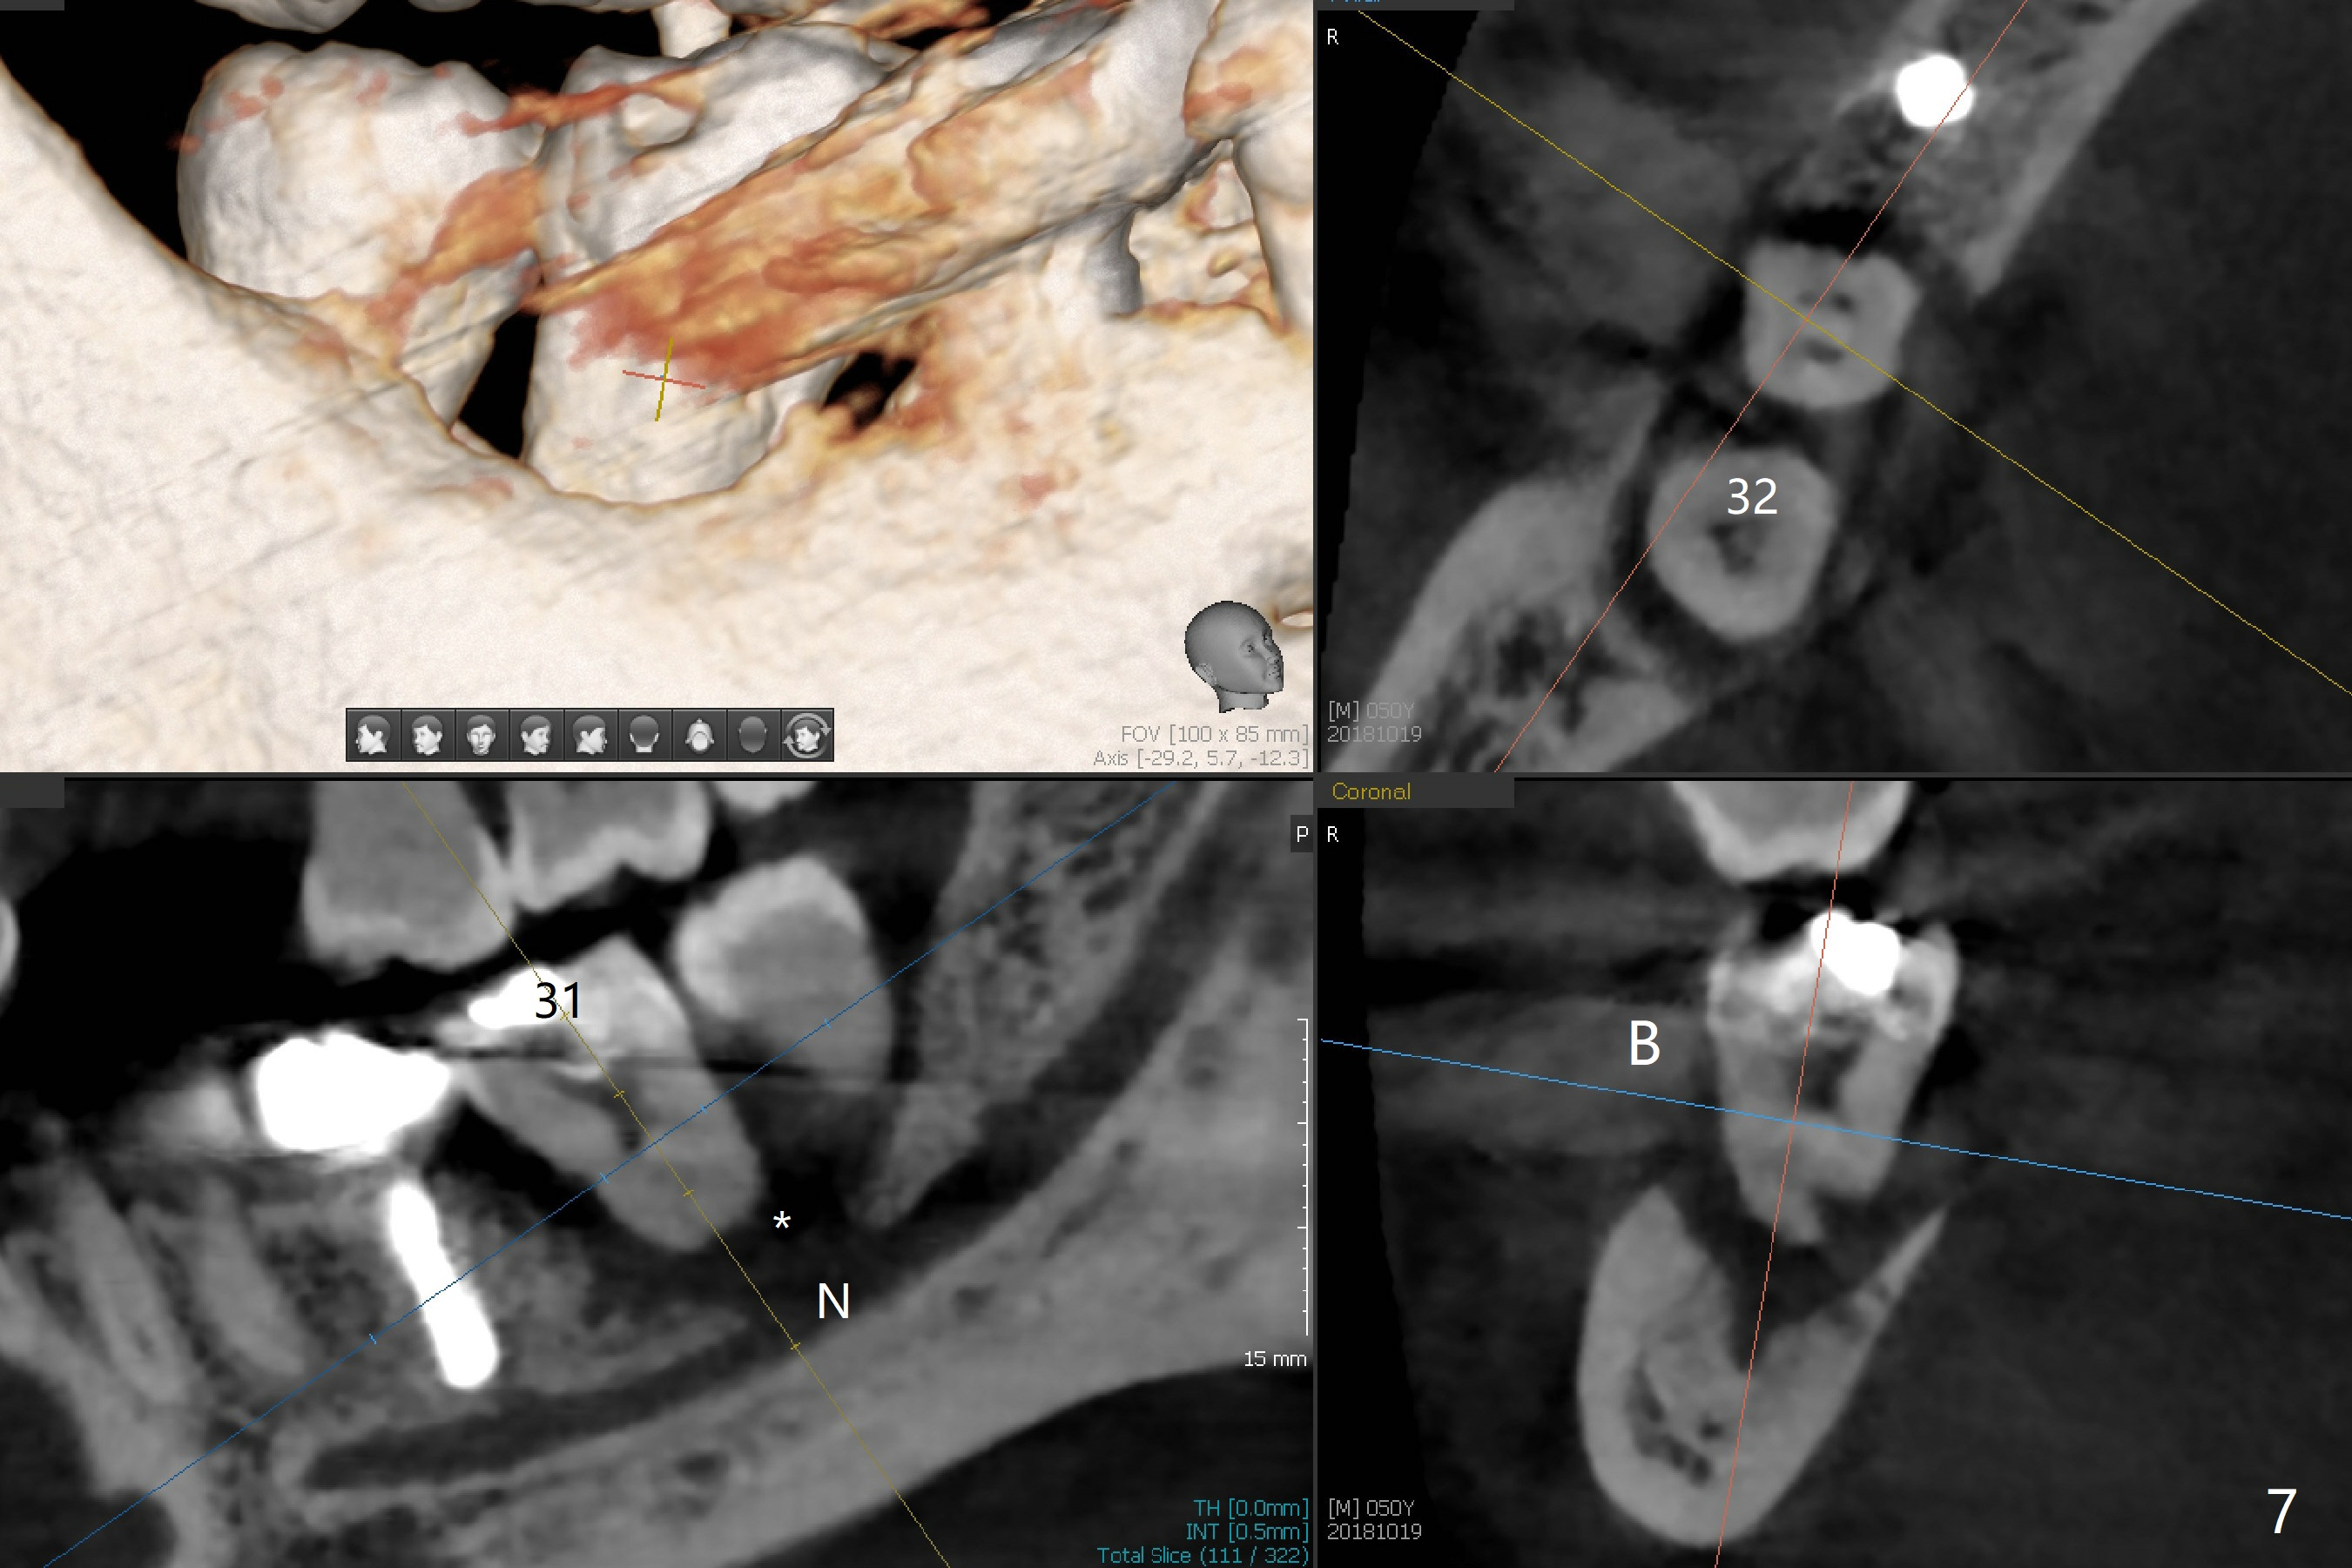

The ridge at #30 is not so narrow (Fig.1). Initial depth is 10 mm with 2 mm from the Inferior Alveolar Canal (Fig.2,3 red dashed line). A 4.5x10 mm implant is placed with > 50 Ncm; a 6.2x5(3) mm healing abutment placed (Fig.4). The implant is stable and seems to be ready for impression 3 months postop (Fig.5). CT taken 5 months post cementation shows that the implant could be placed more lingually (Fig.6 (coronal section; B: buccal)). Periradicular radiolucency at #31 (Fig.7 *) is continuous with the Inferior Alveolar neurovascular bundle (N). After extraction, care should be taken to remove granulation tissue. The tooth #32 will be extracted simultaneously because of severe bone loss.